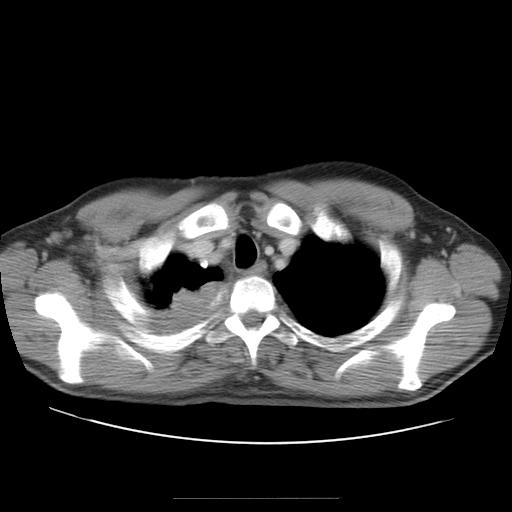

Masse au decours d'un Syndrome de Pancoast-Tobias

Coll. P. Frances

Tomodensimétrie mettant en evidence une masse au niveau de l'apex pulmonaire